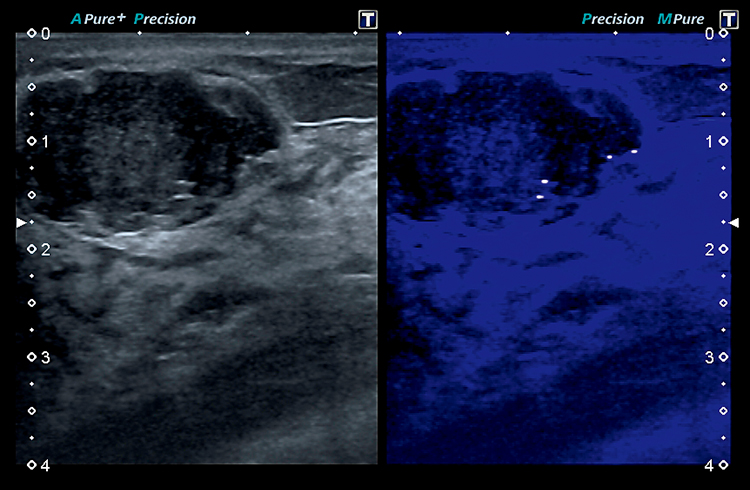

Технология MicroPureTM помогает выявлять микрокальцификаты, позволяет автоматически выявлять микрокальцинаты в виде белых пятен на затененных двумерных изображениях, что обеспечивает проведение более точной биопсии под контролем ультразвукового изображения в 8 реальном времени.

MicroPure - инновационный клинический инструмент, который может помочь вам определить микрокальцификации, потенциальный маркер злокачественности, в молочной железе и других органах. Методика выделяет автоматически обнаруженные кальцификации в виде белых пятен на маскированном 2D-изображении. MicroPure может обеспечить эффективную поддержку точных биопсий под контролем ультразвука в реальном времени.